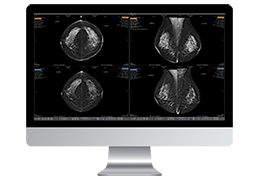

View X-Ray CT & MRI Scans Fast and Easily

FREE and easy to use 3D DICOM Viewer – for surgeons and patient education

Designed for surgeons, Pro Surgical 3D makes it easy to view patient scans quickly. Pro Surgical 3D facilitates the optimal 3D treatment and assessment workflows based on X-ray CT and MRI scans – and best of all, it’s FREE!

Everyone – including surgeons, patients and their loved ones – benefits from being better informed by the wealth of information buried within CT and MRI scans. Pro Surgical 3D gives surgeons more information to develop optimal treatment plans for patients. It also helps patients and their support group better understand their medical condition and proposed treatment options.

Side-by-side comparative assessment for pre- and post-operative scans.